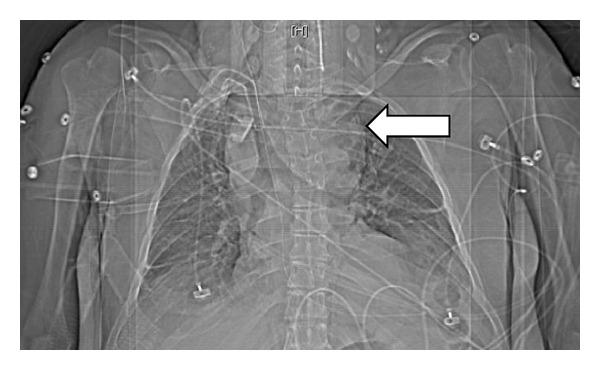

Acute upper airway obstruction is a medical emergency and can be caused by many serious conditions such as a foreign body occluding the airway, intrinsic swelling (as in anaphylaxis), or extrinsic compression. Thyromegaly has rarely been reported as a source of airway compromise. We present a patient whose thyromegaly is presumed to have been induced by lithium and was massive enough to cause severe airway compromise.

急性上气道梗阻是一种医疗急症,可由许多严重情况引起,如气道被异物阻塞、内在肿胀(如过敏反应)或外在压迫。甲状腺肿大作为气道受损的原因鲜有报道。我们报告一例患者,其甲状腺肿大推测由锂盐诱发,肿大程度足以导致严重的气道受损。